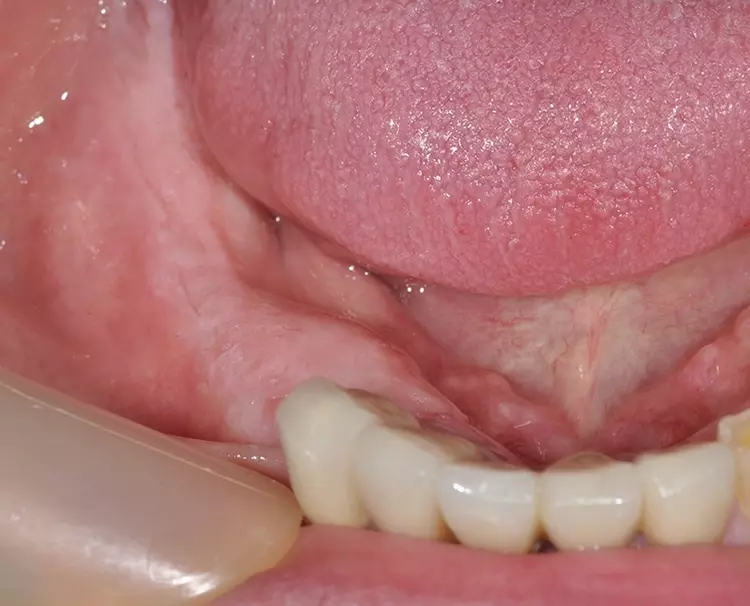

Für das Umsetzen unter Berücksichtigung der genannten Ziele im klinischen Alltag stellen wir einen exemplarischen Behandlungsfall vor. Bei dem 71-jährigen Patienten gilt es, die 2 entstandenen Unterkieferseitenzahnlücken bei guten knöchernen Voraussetzungen implantologisch zu versorgen (Abb. 2 und 3).

Nach dem obligatorischen Nahtverschluss kann nunmehr in der gleichen Sitzung der Intraoralscan erfolgen (Abb. 6). Eingebrachte Heilungskäppchen, die die Multi IM Abutments verschließen, beenden die chirurgische Sitzung (Abb. 7).